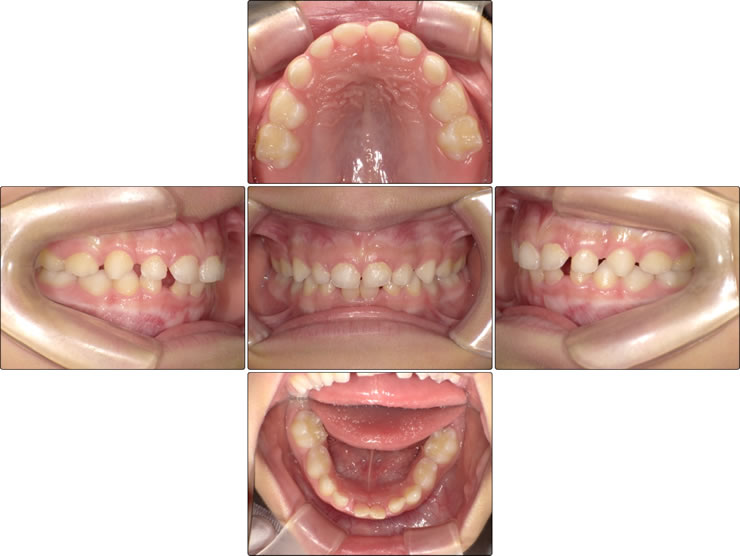

過蓋咬合とは何ですか?

多くの人は、上の歯が下の歯をはるかに越えて伸びていることを表すために「過咬合」という用語を使用します。この歯並びのずれを表す別の俗語は「出っ歯」です。

しかし、矯正歯科医は、下の歯が上の歯と重なることを説明するために過咬合という用語を使用します。次に、上の歯が下の歯をどれだけ突き抜けているかに応じて、過剰咬合を正常から重度に分類します。

過蓋咬合の原因と重症度によって、使用する矯正装置の種類が決まります

過蓋咬合(またはオーバージェット)の原因、重症度、症状によって、どのタイプの矯正器具を使用するのが最適かが決まります。